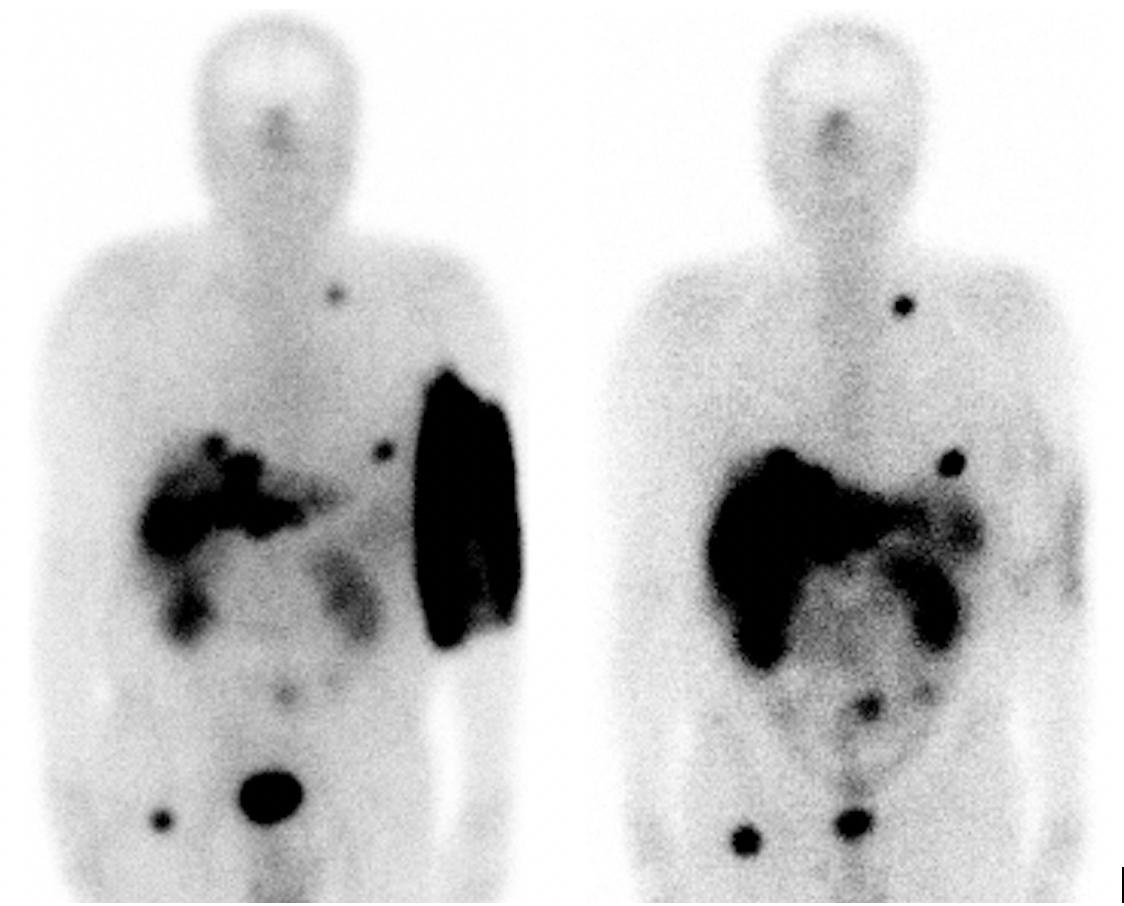

Dans la matinée du 21 septembre 2017, une personne de 70 ans est admise dans notre service pour recevoir une première perfusion lente de lutathera1. Elle vise à traiter une tumeur de l’intestin grêle. L’injection est sur le point de s’achever lorsque l’infirmière supervisant l’acte médical constate un gonflement dans le pli du coude gauche du patient. Face à la suspicion d’extravasation, le traitement est immédiatement interrompu. Le bras est surélevé et enveloppé dans des pansements chauds pour favoriser la diffusion de la radioactivité. Une première scintigraphie de contrôle est réalisée dans la foulée. L’extravasation est confirmée au niveau du membre supérieur. À partir de la dose de Lutathera injectée, de la première scintigraphie et d’une seconde réalisée cinq heures après l’injection, je réalise une estimation approximative de la dose absorbée au niveau du bras de 12 Gy2 en fin de journée. Je communique ces informations aux experts de l’IRSN, qui réalisent une estimation indépendante, proche de la mienne. Le risque de nécrose – observé pour des doses supérieures à 20 Gy – et la nécessité d’un rinçage chirurgical sont alors écartés. Malgré ce résultat, nous demandons au patient de se masser le bras à plusieurs reprises durant la nuit, afin que le médicament continue à se disperser dans l’organisme. Le lendemain matin, deux scintigraphies de contrôle sont réalisées. Elles montrent que la radioactivité a été presque totalement évacuée du bras. Le patient peut rentrer chez lui. Il revient dans le service six jours, puis trois semaines après l’incident pour surveiller l’éventuelle apparition de séquelles liées à l’irradiation. Aucune n’a été détectée.